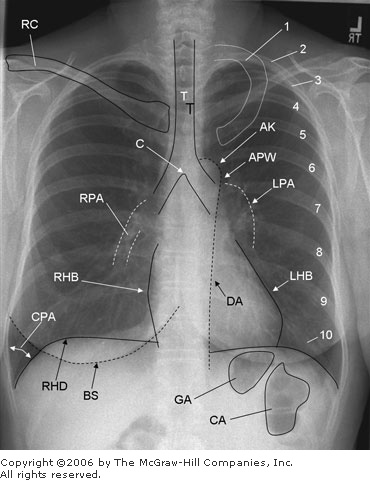

Common X-Ray Studies: Noncontrast Chest Chest X-Ray (Routine): Includes posteroanterior (PA) and lateral chest films. (PA means the film is placed in front of the patient with the beam coming from the back.) Evaluation of pulmonary, cardiac, and mediastinal diseases and traumatic injury. See How to Read a Chest X-Ray, and Figures 15 1 and 15 2. |  | Structures seen on a posteroanterior (PA) chest x-ray. 1 = first rib; 2 10 = posterior aspect of ribs 2 10; AK = aortic knob; APW = aortopulmonary window, BS = breast shadow (labeled only on right); C = carina; CA = colonic air; CPA = costophrenic angle, DA = descending aorta; GA = gastric air; LHB = left heart border (Note: Most of the left heart border represents the left ventricle; the superior aspect of the left heart border represents the left atrial appendage.); LPA = left pulmonary artery; RC = right clavicle (left clavicle not labeled); RHB = right heart border (Note: The right heart border represents the right atrium.); RHD = right hemidiaphragm (left hemidiaphragm not labeled); RPA = right pulmonary artery; T = tracheal air column. |

How to Read a Chest X-Ray A CXR is a basic part of the evaluation of an ill patient. Understanding the basic principles of CXR interpretation is considered a key learning step for all physicians. Determine the Adequacy of the Film - Inspiration: Diaphragm below ribs 8 10 posteriorly and 5 6 anteriorly

PA Film The film is in front of the patient, and the x-ray beam passes from back (posterior) to front (anterior). The following structures are shown in Figure 15 1. Soft Tissues: Check for symmetry, swelling, loss of tissue planes, and subcutaneous air. Skeletal Structures: Examine the clavicles, scapulas, vertebrae, sternum, and ribs. Look for symmetry. In a good x-ray, the clavicles are symmetrical. Check for osteolytic or osteoblastic lesions, fractures, and arthritic changes. Look for rib-notching. Diaphragm: Sides should be equal and slightly rounded, although the left is usually slightly lower by one rib interspace. Costophrenic angles should be clear and sharp. Blunting suggests scarring or fluid. It takes about 100 200 mL of pleural fluid to cause blunting. Check below the diaphragm for the gas pattern and free air. A unilateral high diaphragm suggests paralysis (from nerve damage, trauma, or an abscess), eventration, or loss of lung volume on that side because of atelectasis or pneumothorax. A low, flat diaphragm suggests COPD. Mediastinum and Heart: The aortic knob should be visible and distinct. Widening of the mediastinum is seen with traumatic disruption of the thoracic aorta. In children, do not mistake the normally prominent thymus for widening. Mediastinal masses can be associated with Hodgkin disease and other lymphomas. The trachea should be in a straight line with a sharp carina. Tracheal deviation suggests a mass (tumor), goiter, unilateral loss of lung volume (collapse), or tension pneumothorax. The heart should be less than one-half the width of the chest wall on a PA film. If greater than one half, consider the presence of CHF or pericardial fluid. Hilum: The left hilum should be up to 2 3 cm higher than the right. Vessels are seen. Look for any masses, nodes, or calcifications. Lung Fields: Note the presence of any shadows from CVP lines, NG tubes, pulmonary artery catheters, etc. The fields should be clear with normal lung markings all the way to the periphery. The vessels should taper to become almost invisible at the periphery. Vessels in the lower lung should be larger than those in the upper lung. A reversal of this difference (called cephalization) suggests pulmonary venous hypertension and heart failure. Kerley B lines, small linear densities found usually at the lateral base of the lung, are associated with CHF. Check the margins carefully; look for pleural thickening or calcification, masses, and pneumothorax. If the lungs appear hyperlucent with a relatively small heart and flattening of the diaphragms, COPD is likely. Thin, plate-like linear densities are associated with atelectasis. To locate a lesion, do not forget to check a lateral film and remember the "silhouette sign." Obliteration of all or part of a heart border means the lesion is anterior in the chest and lies in the right middle lobe, lingula, or anterior segment of the upper lobe. A radiopacity that overlaps the heart but does not obliterate the heart border is posterior and lies in the lower lobes. Examine carefully for the following: | | 1. Coin lesions: Caused by granulomas (50% of cases and usually calcified and caused by histoplasmosis, 25%; TB, 20%, or coccidioidomycosis, 20%; varies with locale); primary carcinoma (25%), hamartoma (< 10%), and metastatic disease (< 5%) 2. Cavitary lesions: Caused by abscess, cancer, TB, coccidioidomycosis, Wegener granulomatosus 3. Infiltrates: Two major types | | a. Interstitial Pattern. "Reticular." Caused by granulomatous infections, miliary TB, coccidioidomycosis, pneumoconiosis, sarcoidosis, CHF. "Honeycombing" represents end-stage fibrosis caused by sarcoid, RA, and pneumoconiosis. b. Alveolar Pattern. Diffuse, quick progression and regression. "Butterfly" pattern or air bronchograms. Caused by PE, pneumonia, hemorrhage, or PE associated with CHF. |